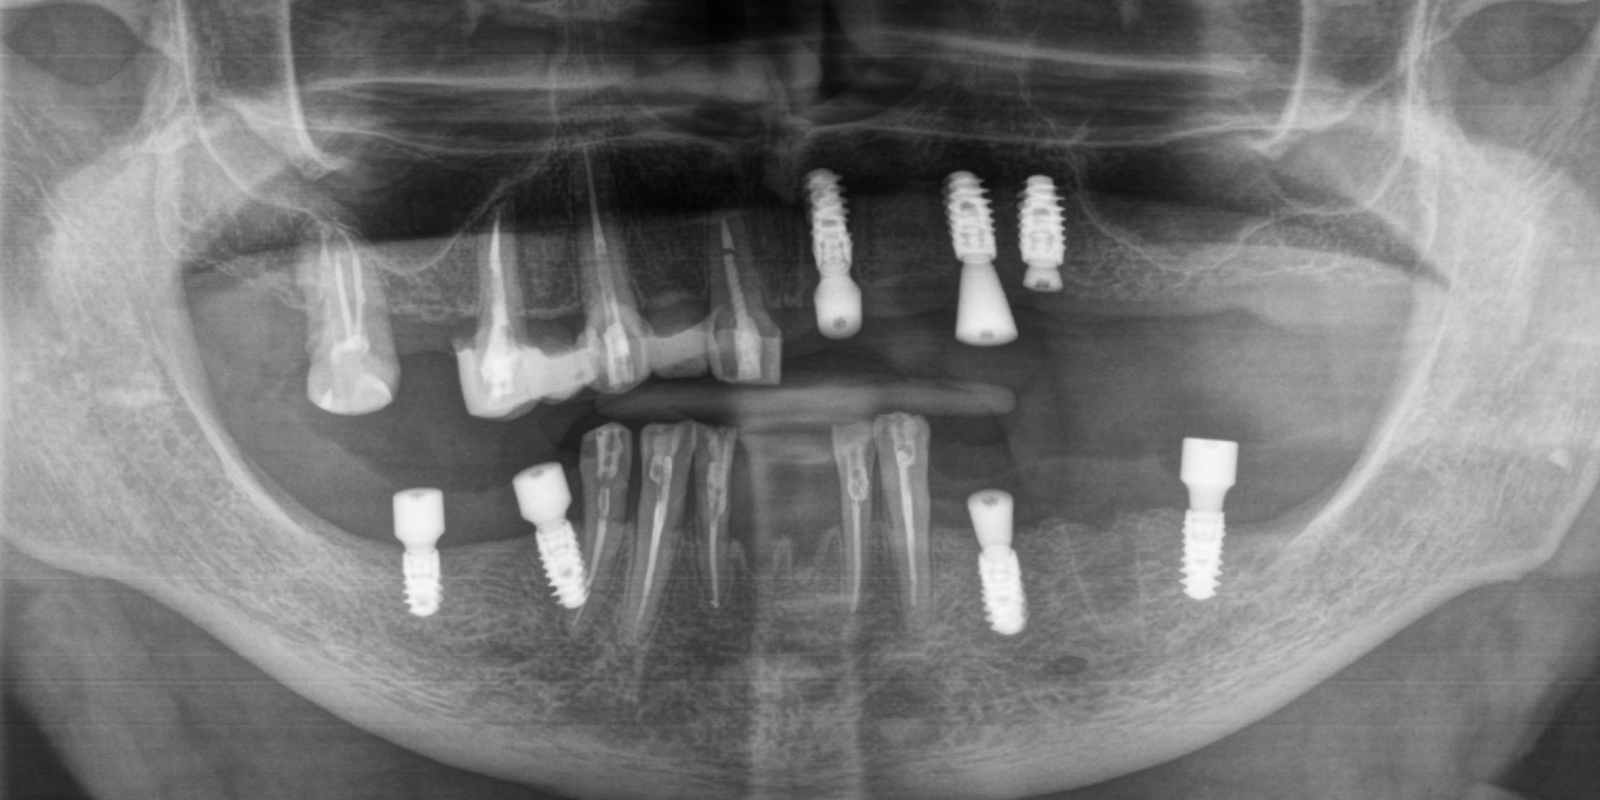

Мы провели осмотр и компьютерную томографию, чтобы оценить состояние кости и оставшихся зубов. Выяснилось: несколько зубов ещё можно сохранить, но значительную часть необходимо было удалять. На основе диагностики мы предложили комплексный план лечения.

- Установить 7 имплантатов Straumann BLX (3 на верхней челюсти слева, 2 слева внизу, 2 справа внизу).